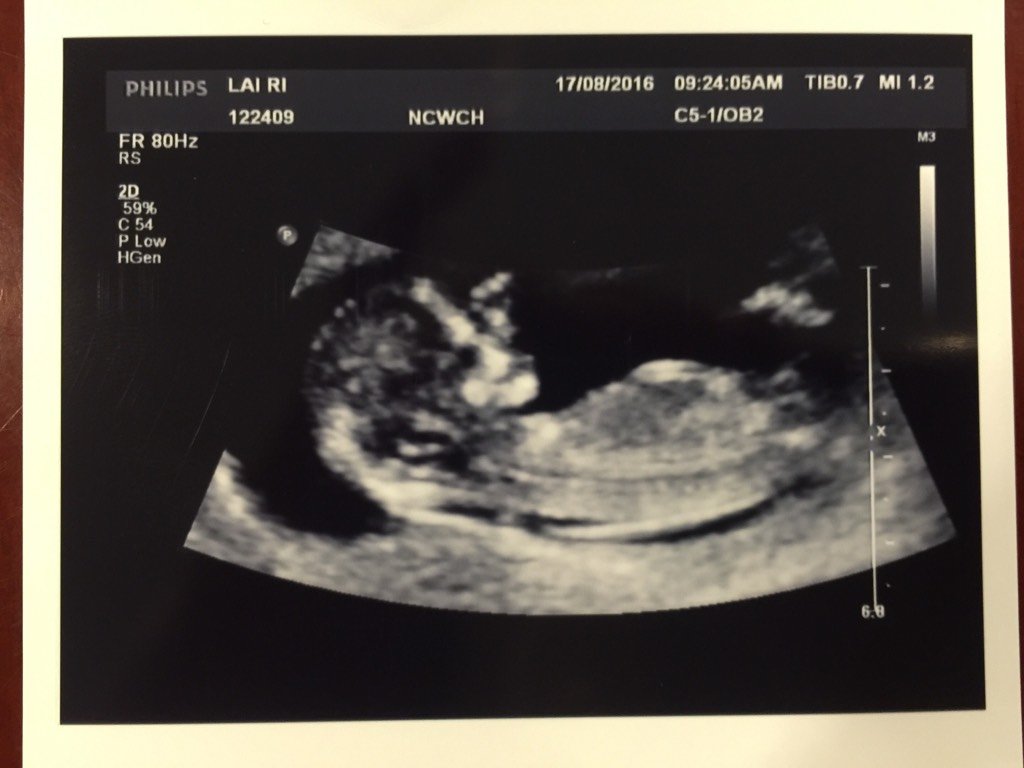

NT